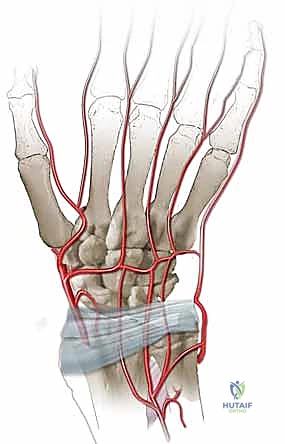

التروية الدموية: نقطة الضعف القاتلة

السبب الجذري لمرض كينبوك يكمن في التروية الدموية الفريدة (والهشة أحياناً) للعظم الهلالي. تتلقى معظم العظام الدم من عدة أوعية دموية تدخل من اتجاهات مختلفة. ومع ذلك، في حوالي 20% إلى 30% من البشر، يتلقى العظم الهلالي إمداده الدموي من وعاء دموي واحد فقط (Single Volar or Dorsal Artery). إذا تعرض هذا الوعاء الدموي الوحيد للانسداد، أو التمزق بسبب صدمة، أو الضغط المستمر، فإن العظم يُحرم من الأكسجين والمواد المغذية، مما يؤدي إلى بداية عملية النخر (موت الخلايا العظمية).

الهدف من هذا الإجراء هو جلب دم جديد وصحي إلى العظم الهلالي الميت لإنقاذه من الانهيار والسماح له بإعادة بناء نفسه.

3. الجزء الحاسم: لا يتم أخذ العظم فحسب، بل يتم استئصاله مع الشريان والوريد المتصلين به (Pedicled graft). هذا يعني أن قطعة العظم المنقولة لا تزال حية وتنبض بالدم.

6. تعمل الأوعية الدموية المنقولة كـ "شريان حياة" جديد، حيث تبدأ في تغذية العظم الهلالي، مما يحفز الخلايا العظمية (Osteoblasts) على بناء نسيج عظمي جديد وقوي.